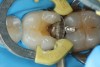

Fig 4. Removing soft infected dentin.

Figure 4

To determine how much to remove, it is important to understand the difference between infected dentin and affected dentin. The infected layer of dentin is highly demineralized, is physiologically unable to remineralize, and contains irreversibly denatured collagen fibrils with a virtual disappearance of cross-linkages.18 It contains bacteria and degraded collagen that cannot be remineralized. On the other hand, the affected dentin has a minimal concentration of bacteria, and the collagen network is still viable.19 Clinically, affected and infected dentin are differentiated by their hardness. Infected dentin is soft and can be easily removed with a spoon excavator (Figure 4). Affected dentin is leathery and requires firm pressure to be removed with a spoon excavator (Figure 5).20